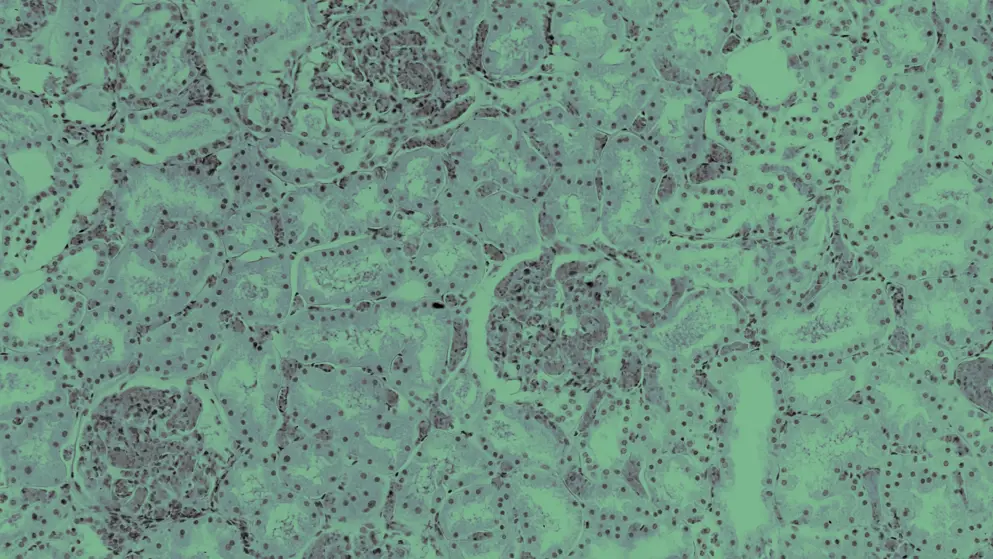

Chronic kidney disease

Glomerulonephritis